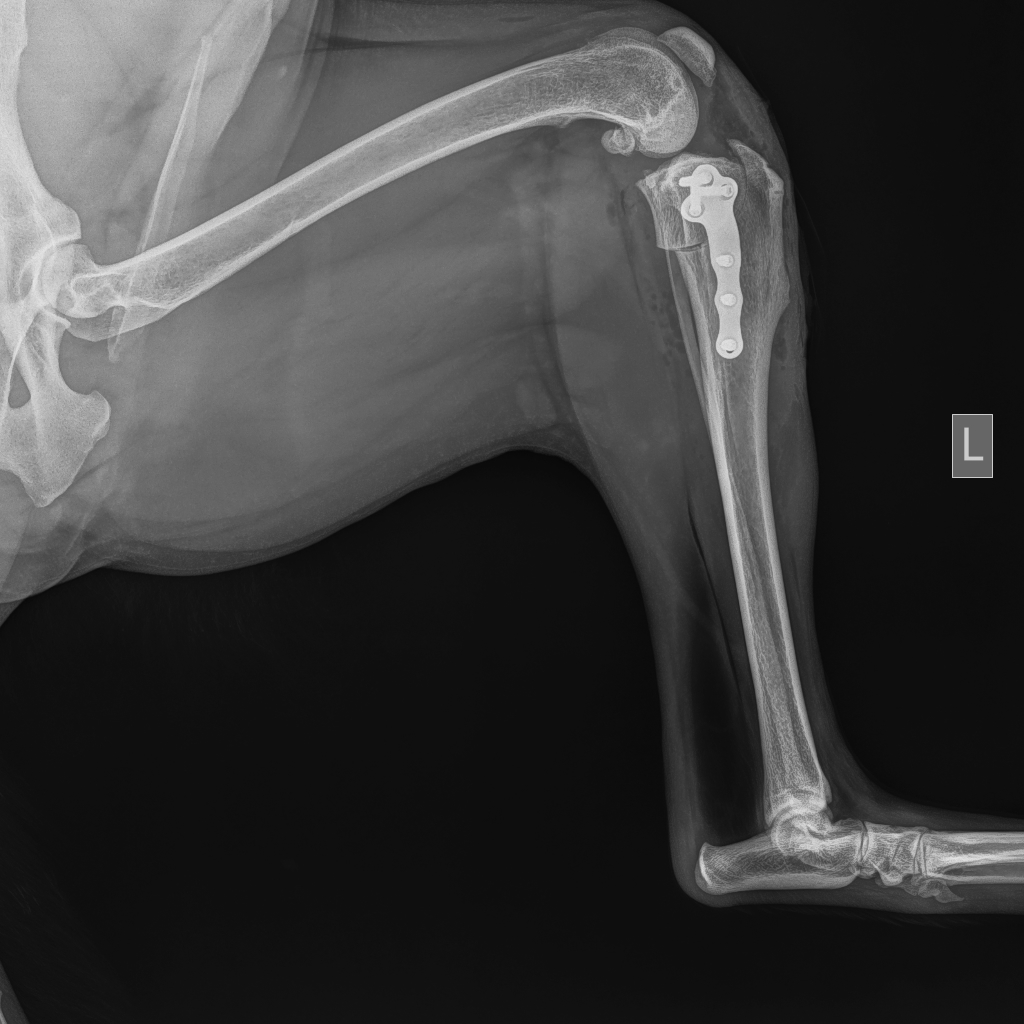

Op een röntgenfoto is vaak zichtbaar of boven- en onderbeen ten opzichte van elkaar verschoven zijn. Bij een gedeeltelijke scheuring is die abnormale beweging of verplaatsing er niet. Het is van belang te weten hoe ernstig het gewricht ontstoken is en hoeveel botwoekering (artrose) al is opgetreden. Botwoekeringen zijn op een röntgenfoto zichtbaar. De artrose kan niet verwijderd worden.

De TPLO (Tibial Plateau Leveling Osteotomy) techniek is gebaseerd op het wegnemen van de voorwaartse stuwkracht van het scheenbeen door de helling van de bovenkant (plateau) van het scheenbeen te verminderen. Hierdoor verdwijnt bij een normale beweging van de knie de belasting op de voorste kruisband. Door middel van de TPLO zal dus een evenwicht tussen gewichtsbelasting en de actieve spierkrachten ontstaan en is er verder geen extra behandeling voor de stabiliteit van de knie noodzakelijk.

Na de operatie is er een revalidatie periode noodzakelijk. De eerste 14 dagen na de operatie moet er absolute bench- of hok-rust gegeven worden. Dat houdt in dat uw hond alleen voor behoefte (aan korte lijn) naar buiten mag en daarna weer bench-rust moet krijgen. De 8 weken daarna krijgt u een bewegings-schema mee waarbij de hond aan de korte lijn langzaam steeds iets meer mag lopen. Acht weken na de operatie zullen er röntgenfoto’s gemaakt worden om te controleren of er een goed herstel is.